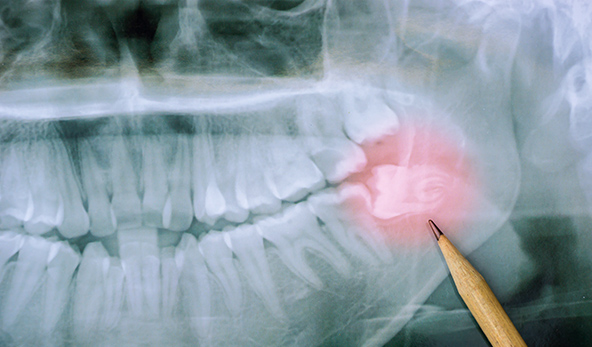

사전 정밀분석

사랑니 발치가 필요한 경우, 치과 의사는 환자의 구강 상태를

정밀하게 분석합니다. 이를 위해 X선이나 CT 스캔을 이용하여

사랑니의 위치, 크기, 각도, 주변 조직과의 관계 등을 확인합니다.

사랑니 발치가 필요한 경우, 치과 의사는 환자의

구강 상태를 정밀하게 분석합니다.

이를 위해 X선이나 CT 스캔을 이용하여 사랑니의 위치,

크기, 각도, 주변 조직과의 관계 등을 확인합니다.